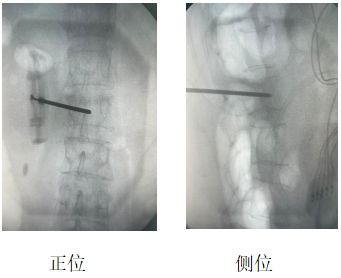

患者辛某(化名),女性,69歲,因“腰部劇烈疼痛伴活動(dòng)受限2天”入院。既往有骨質(zhì)疏松癥病史,影像學(xué)檢查提示L2椎體新鮮壓縮性骨折,VAS評(píng)分8分。

當(dāng)?shù)蒯t(yī)院建議外科手術(shù)治療,患者及家屬拒絕開刀手術(shù),遂來我院疼痛科。結(jié)合患者自身情況,劉康主任與科室人員經(jīng)討論,決定行“經(jīng)皮椎體成形術(shù)(PVP)”聯(lián)合“脊神經(jīng)后內(nèi)側(cè)支射頻調(diào)控術(shù)”,同時(shí)解決椎體穩(wěn)定性與神經(jīng)源性疼痛問題。

劉康主任表示,椎體成形術(shù)+脊神經(jīng)射頻調(diào)控聯(lián)合應(yīng)用,較傳統(tǒng)單一“骨水泥”植入對(duì)緩解疼痛有明顯改善。

兩者微創(chuàng)聯(lián)合優(yōu)勢(shì)應(yīng)用于“椎體壓縮骨折”可單次麻醉、同一體位完成兩項(xiàng)操作,降低手術(shù)風(fēng)險(xiǎn),提升患者耐受性,顯著緩解疼痛,大大減少“骨水泥”植入術(shù)后殘余疼痛。  脊神經(jīng)后內(nèi)側(cè)支射頻是骨質(zhì)疏松性壓縮骨折(OVCFs)疼痛管理的重要補(bǔ)充。約30%患者“骨水泥”植入術(shù)后存在脊神經(jīng)源性殘留痛,聯(lián)合射頻可顯著提升遠(yuǎn)期療效。此病例為骨質(zhì)疏松性骨折的個(gè)體化治療提供了新思路。